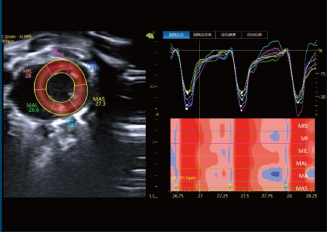

超分辨超声成像是一种前沿超声技术,传统超声成像系统在分辨率与穿透力之间具有经典矛盾,其分辨率极限受限于波长,波长越短,超声波吸收显著增加,严重限制其成像深度。传统超声分辨率在百微米左右。超声超分辨成像与传统超声相比,分辨率增加至少十倍,同时保持了传统超声成像系统的穿透力与视野。在无创的前提下,为更高时间分辨率的血管动态成像带来了机会。在癌症、神经疾病、肾脏疾病等与微血管系统密切相关的疾病研究领域有着广泛的应用前景。

LTIMUS9LAB具备的SMF功能可通过检测脑血管流量变化代替脑活动变化,并有如下特点:

●实时成像

●≤1ms 超高时间分辨率

●≤30μm高空间分辨率

●灵敏度可达传统超声成像的100倍

●单次扫描成像

●清醒活动成像